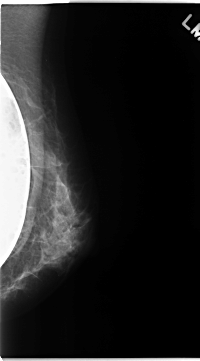

C_0134_1.LEFT_MLO

LEFT_MLO LINES 4688 PIXELS_PER_LINE 2592 BITS_PER_PIXEL 12 RESOLUTION 50 NON_OVERLAY